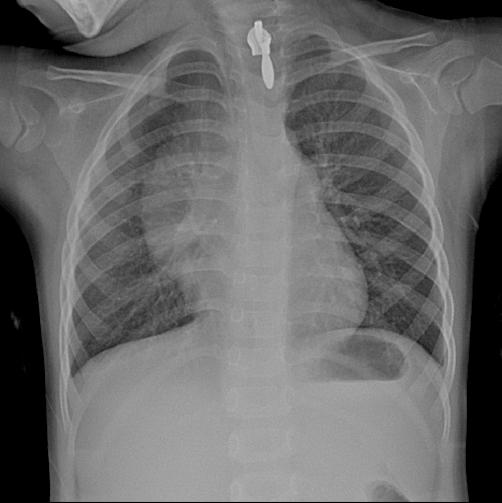

女,4岁,低烧四天,无咳嗽。请各位点评。

纵隔增宽,胸腺瘤可能性大,建议加照侧位。

纵隔像有占位性病变,建议做胸部ct检查。

右中上纵隔增宽,气管未见变形移位,可能是后纵隔及脊柱旁的,建议进一步检查。

右中上纵隔占位性病变,不排除畸胎瘤可能;建议行ct扫描检查。

有结果了,经中山大学一附院诊断为正常胸腺增大。有点惊讶!小孩胸腺增大本属正常,但如此大也在正常范围?算是长见识了!